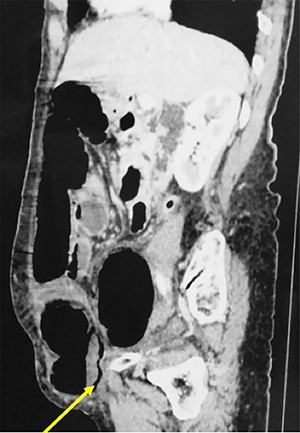

An 84-year-old patient, gravida 8, para 8, consulted in emergency department for abdominal pain and vomiting evolving for 7 days. The blood pressure was 120/70 mm Hg with a fever at 38.6°. The physical examination found an ovoid non-reducible mass of the right lower quadrant (Fig. 1). There was no abdominal tenderness or peritoneal signs. The computed tomography (CT) scan showed a strangulated right spigelian hernia with a hernial ring measured to 3.4 cm. The content was the coecum (Fig. 2). There were also signs of bowel ischemia with pneumatosis and minimal peritoneal effusion (Fig. 3). Biology found leukocytosis at 15 200 elements per mm3. Surgical exploration with an incision centered on the mass confirmed the diagnosis. There was an extensive necrosis of the hernial sac and its contents (the caecum, appendix and 10 cm of the terminal ileum) (Figs 4 and 5). A right hemi-colectomy with an ileo-colic anastomosis was performed. The parietal defect was closed by an aponeurorraphy with Mersuture 0. The post-operative course was marked by the death of the patient in intensive care due to multi-visceral failure.

Abdominal CT scan showing a strangulated right spigelian hernia with pneumatosis (arrow).